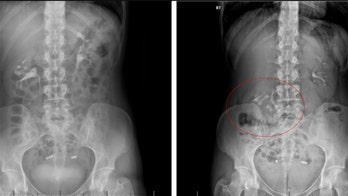

April 23, 2018 Woman diagnosed with rare 'floating kidney' condition Generally, you can trust your organs to stay in one place.